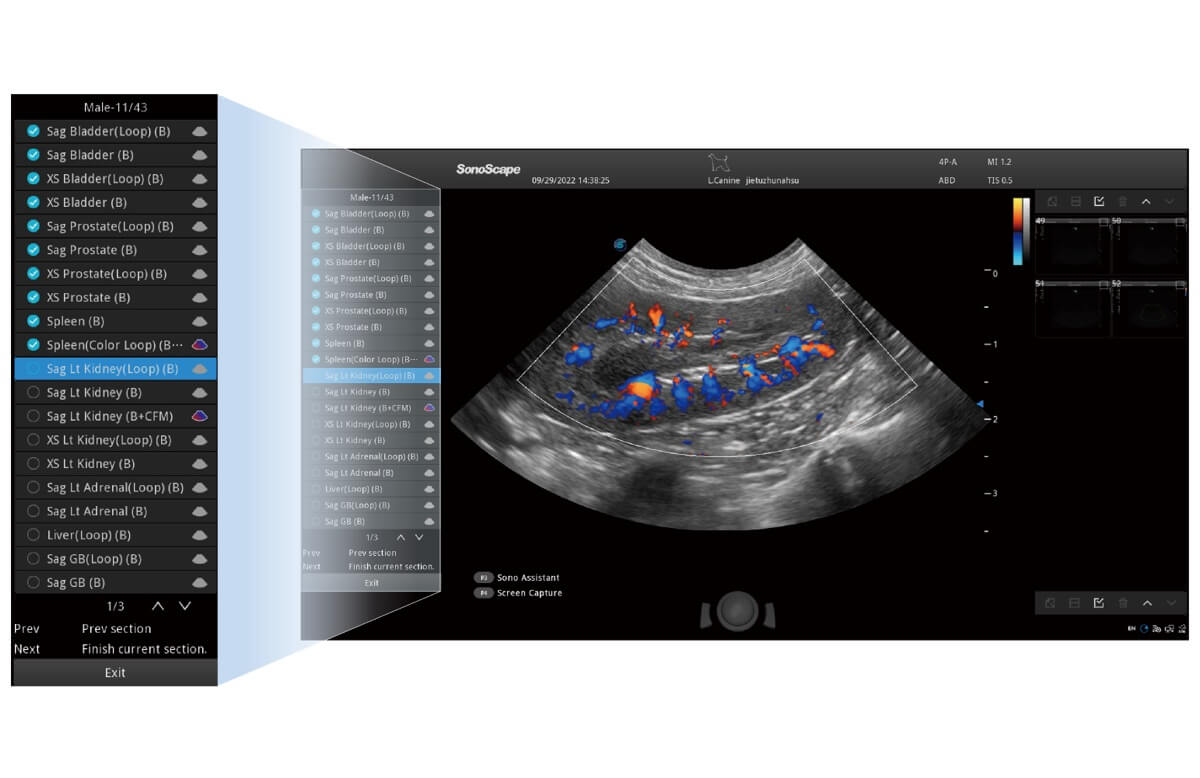

Das ProPet wurde für Tierärzte entwickelt, um ein sehr hohes Maß an Professionalität bei allen tierärztlichen Anwendungen sicherzustellen. Mit der auf den Tierarzt zugeschnittenen Software erhalten Sie eine intuitive Bedienung und schnellstmöglich eine genaue Diagnostik.

Erleichtert die Auswahl aus einer Liste von Tierarten, Schallköpfen und Kombinationen von Voreinstellungen mit nur einem Klick.

Führt den Anwender durch die gesamte Untersuchung und bietet zur Optimierung des Arbeitsablaufs und Erhöhung der Standardisierung individuell konfigurierbare Protokolle.